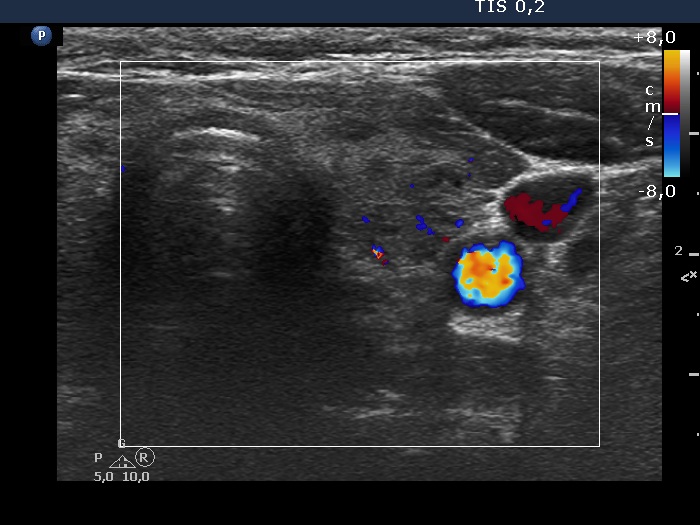

Discrete lesion or nodule in Hashimoto's thyroiditis - case 33 (1650) (ultrasonographic picture 12)

Left lobe, transverse scan, color Doppler mode. The vascularization is not specific .